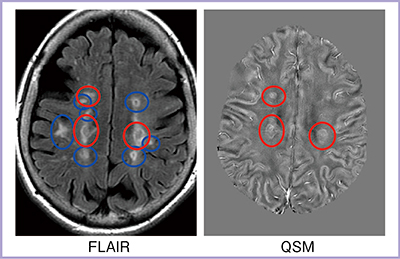

多発性硬化症では脱髄斑(プラーク)で磁化率の上昇が認められる。図1のように,FLAIRでは高信号として認められQSMでは磁化率に変化が見られないプラーク(○)もあるが,これは磁化率が経時的に変化するためである。急性期プラークは磁化率がほとんど上昇しないが,数年経つと磁化率が上昇して数年にわたり高い状態が続き,その後,元に戻ることが報告されている1),2)。時間の経過に伴ってプラーク内に鉄沈着が生じ,また,脱髄(反磁性体であるミエリンの障害)により磁化率が上昇するという機序が考えられている。

図1 多発性硬化症のFLAIRとQSM